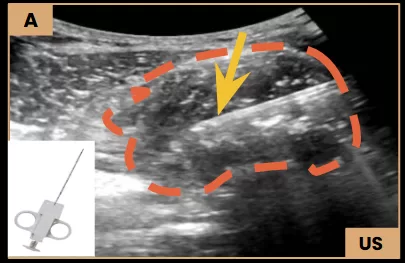

Ultrasound-Guided Biopsy

Image A: Ultrasound-guided biopsy using a Tru-Cut needle (arrow) obtained multiple soft tissue cores.

Soft Tissue Biopsy

Image A: US-guided biopsy showing the Tru Cut needle (arrow) sampling the soft tissue component (dashed line) of the tumor.